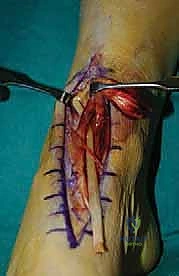

2. الشق الجراحي والوصول للوتر

يتم عمل شق جراحي طولي (Anteromedial Incision) في الجزء الأمامي الداخلي للكاحل والقدم. يتم التعامل مع الأنسجة الرخوة بأقصى درجات الحذر لحماية العصب الشظوي السطحي والأوعية الدموية.

5. إعادة توجيه وتر EHL (Tendon Routing)

وهي خطوة حاسمة لنجاح البيوميكانيكا. يتم تمرير وتر EHL المستخلص عبر الغمد الخاص بوتر الظنبوب الأمامي الممزق، أو تحته، لضمان أن يكون خط الشد (Line of Pull) مطابقاً تماماً للوتر الأصلي، مما يضمن رفع القدم بشكل متوازن دون انحرافها للخارج أو الداخل.